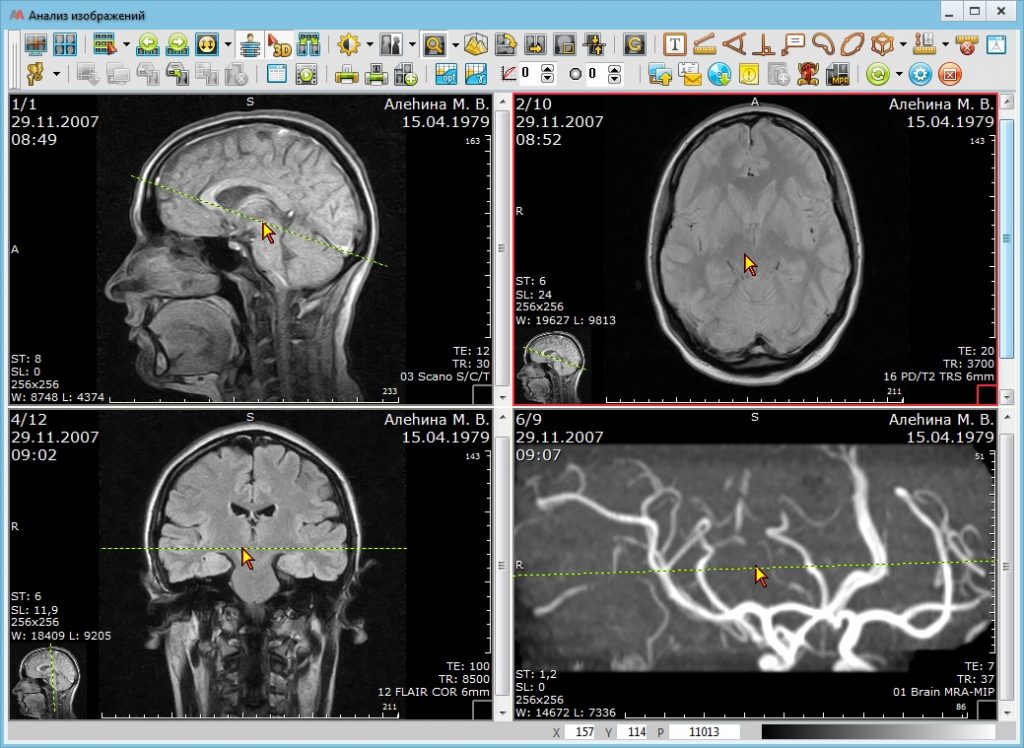

АПК АрхиМед отличается надежностью и широким функционалом. Простой и удобный интерфейс поможет эффективно организовать работу с исследованиями. С нашей системой получить качественное исследование стало проще и быстрее.

Некоторые функциональные возможности и характеристики программного обеспечения АПК АрхиМед

- Раскладка серий изображений

- Функция 3D курсора (автоматическое указание местоположения выбранной точки изображения на изображениях других серий с синхронизацией при навигации)

- Мультипланарная реконструкция (MPR) выбранной серии изображений во взаимно перпендикулярных плоскостях